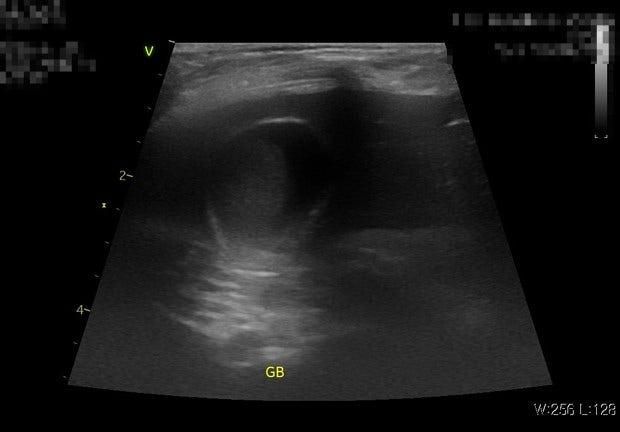

병원을 각기 다른 두곳을 다녔는데 모두 슬러지라 했으며 우루사 처방은 안해줬습니다 11살 토이푸들 4kg 수컷 강아지 입니다 ALP 수치 정상이였습니다

혹시 이 담낭 상태로 인해 부분적으로 겉에만 시멘트 회색변을 눌 가능성이 있을까요?

슬로지어도 다 수술하는 것이 아닙니다. 초음파나 혈액 검사 등으로 확실하게 탐랑 전액 좀 이 진단이 되는 경우에는 수술적인 담낭 제거술이 지시됩니다